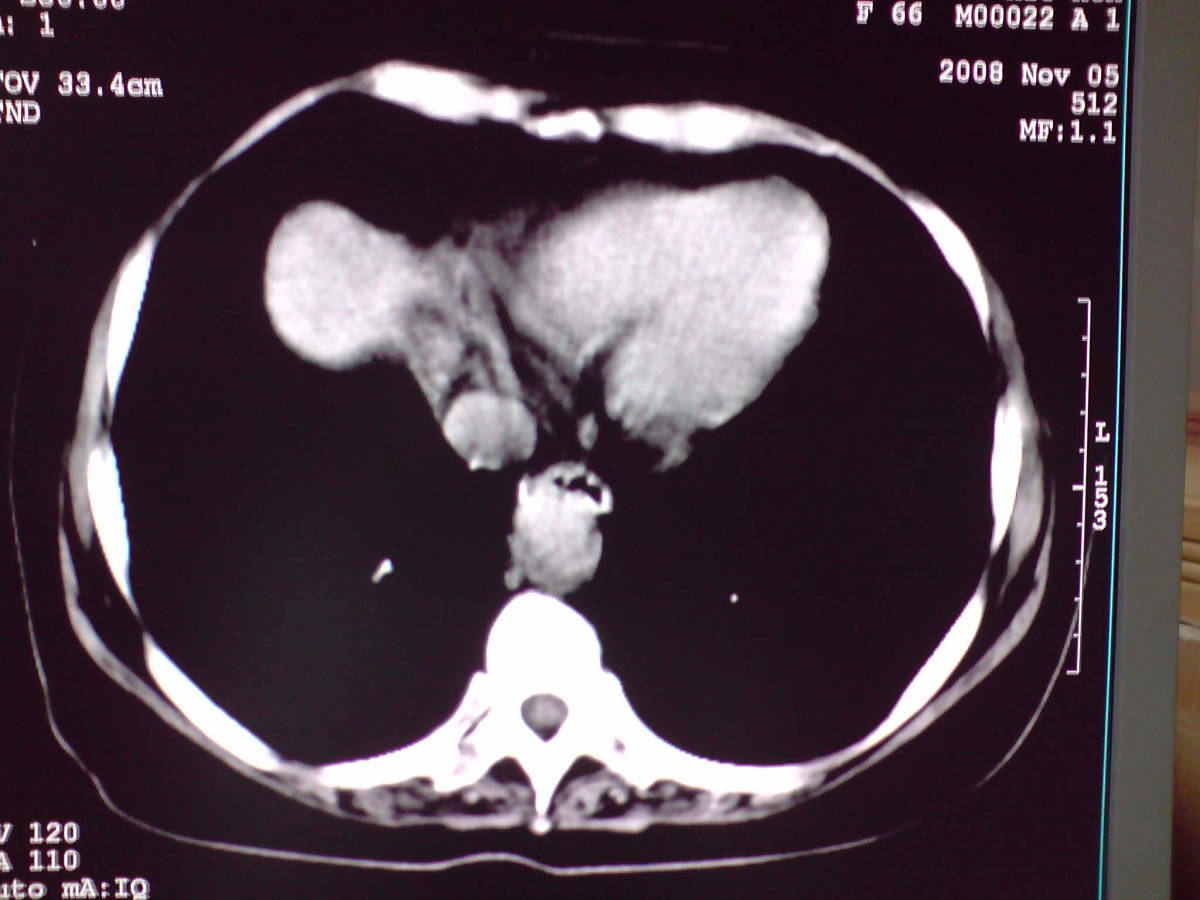

女性,60岁,上腹不适、自感胃部疼痛

小网膜区见类圆形软组织密度肿块,密度不均,内见不规则低密度区,与肝左叶分界模糊,肝脏体积缩小,密度不均匀,边缘呈波浪状,尾状叶明显增大,脾脏下缘明显超出肝脏下缘。

意见:肝硬化并外生性肝癌,建议增强扫描。

肝脏比例失调,形态失常,外缘呈波浪状,腹腔内肿块内见低密度区并与肝脏界限欠清

考虑外生性肝癌,左肺下叶占位,肝硬化

有肝硬化背景,肝胃间隙见不规则形,且密度不均匀的占位性病变,与肝左叶分界不清,首先考虑外生性肝癌可能性大,不排外肝胃间隙恶性占位肝脏受侵可能性。左肺下叶结节影,其内见空泡征,边缘见毛刺,从一元化的角度首先考虑转移。

1 肝脏各叶比例失调,形态失常,外缘呈波浪状。右叶萎缩,左叶 尾叶增大。2 腹腔内软组织密度肿块,低于肝实质密度,内见低密度区,并与肝脏界限欠清。腹膜后见肿大淋巴结,并与腹腔肿块关系密切。3 左肺下叶肿块,见边缘毛刺征及胸膜凹陷征,并与近肺门侧见异常血管相连。

综合考虑:左下肺周围性肺癌伴腹腔 腹膜后淋巴结转移!另:肝硬化!

1肝胃韧带区域一肿块,肿块上缘与肝左叶相连。肝硬化。考虑肝外生型肝癌可能性大,不除外间质瘤。2左肺下叶背段一结节,有偏心性空洞,长毛刺,其周有多发小结节。考虑结核可能性大。

感谢大家的讨论,今天拿到病理结果是肝细胞癌